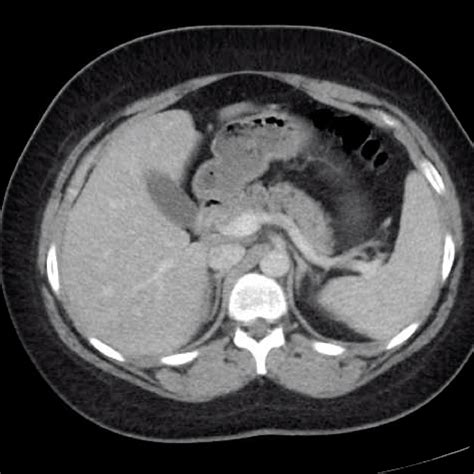

• Imaging Studies: Ultrasound, CT scan, or MRI can provide detailed images of the spleen and help diagnose conditions such as splenomegaly or splenic rupture.

• Imaging Studies: Ultrasound, CT scan, MRI, or endoscopic ultrasound can provide detailed images of the pancreas and help diagnose conditions such as pancreatic cancer or pancreatitis.

• spleen and pancreas anatomy

• spleen and pancreas location